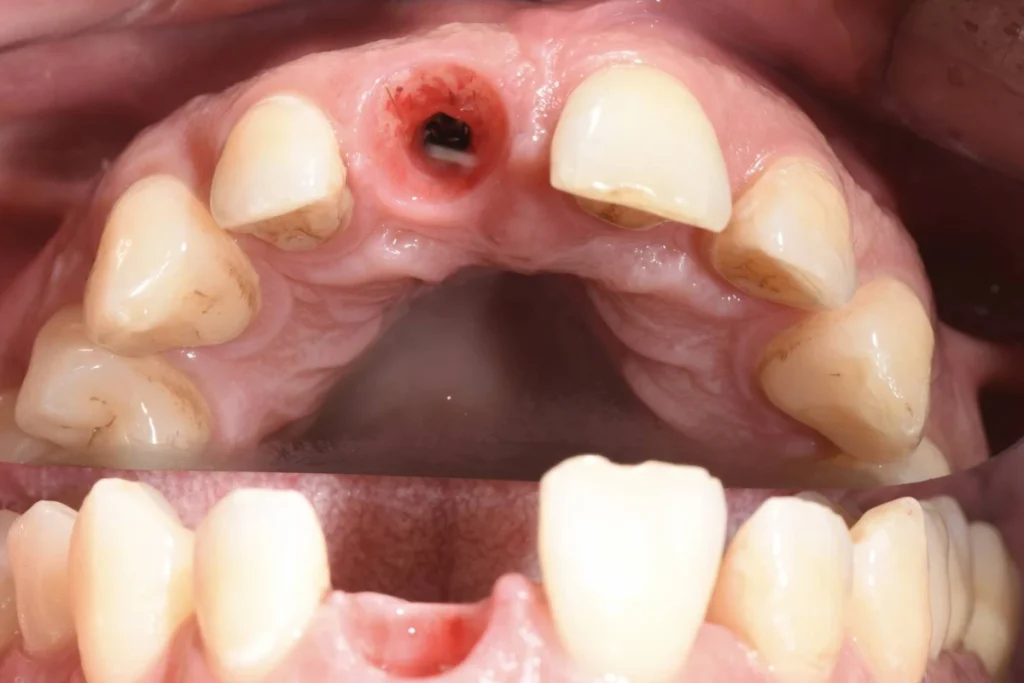

L’intervention est réalisée sous anesthésie locale et doit être complètement indolore. Le patient est revu 3 mois après l’intervention pour prendre une empreinte. Le patient est invité à se rendre au laboratoire de prothèse situé dans le 17ème afin de discuter de la forme de la dent avec l’artisan céramiste. Dans le cas présent, il souhaitait conserver l’écart existant entre ces incisives afin de conserver l’identité de son sourire.

Lors de cet entretien, le prothésiste enregistre également toutes les données de teinte et d’état de surface des dents adjacentes afin de faire la parfaite illusion d’une dent naturelle.

Environ une semaine après la prise de l’empreinte, un essayage est réalisé au cabinet. Si tous les paramètres esthétiques et fonctionnels sont validés, la couronne est posée dans la foulée.

Il est parfois nécessaire de prendre le temps d’une retouche au laboratoire afin d’obtenir le rendu escompté.